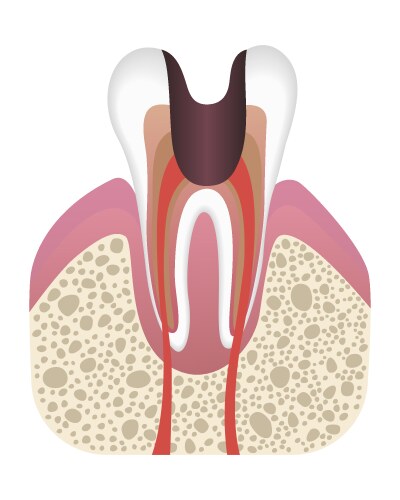

- Caries

- Stage

- Tooth

- Development

- Structure

- Decay

- Dental

- Enamel

- Abscess

- Anatomy

- Dentin

- Pulp

- Molar

- Periodontitis

- Root